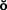

Panoramic films (Fig. 1-24) provide useful information about the presence or absence of teeth. They are especially helpful in assessing third molars and impactions, evaluating the bone before implant placement (see Chapter 13), and screening edentulous arches for buried root tips. However, they do not provide a sufficiently detailed view for assessing bone support, root structure, caries, or periapical disease.

Fig. 1-24 A panoramic film cannot be substituted for a full-mouth series because the image is distorted. Nevertheless, it is very useful for assessing unerupted teeth, screening edentulous areas for buried root tips, and evaluating the bone before implant placement.